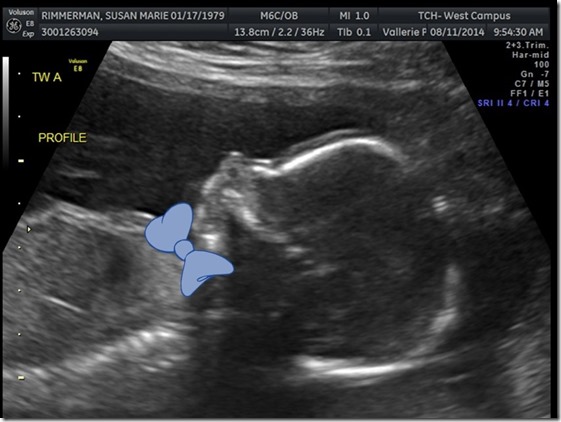

Was your guess correct! August 16, 2014 By srimmerman We are super excited to share what baby Rimm A and baby Rimm B are! Both boys are happy and healthy! Baby RImm A is 12oz and Baby Rimm B is 11oz. They are both VERY active and I’m sure going to be giving us a run for our money once they are born!! Share this: Share on X (Opens in new window) X Share on Facebook (Opens in new window) Facebook Like Loading... Related